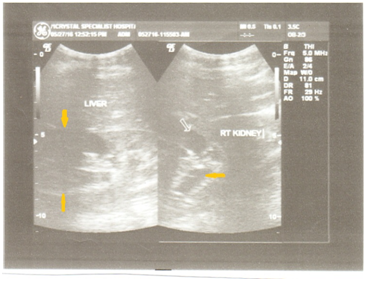

By July 2016 (see sonograms), no reflux in patient was observed post-micturition cystography. At present, December 2016, after follow-up presentation for ultrasound, increased urination averaging 29 times/day, with stable kidney function; serum creatinine: 1.48 mg/δl. Though some patients have undergone surgical procedure to alleviate functional obstruction,8 it is advisable treatment is medical. Instruction to patients on the importance of early frequent voiding cannot be overemphasized. The RT kidney (Figure 1) measured 118 x 62mm in longitudinal and AP diameters, LT kidney (Figure 3&4) dimension was 120 x 65mm before progression.

Figure 3 LT renal bulge with AP diameter of 65mm, observe severe dilation of the lower pole overlying cortical thinning (see arrow) and minor calyces. The patient laid in both supine and decubitus positions. Observe the hydronephrotic (H) accumulation.